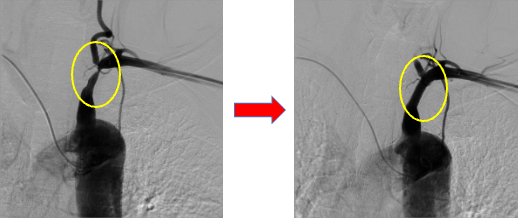

下にいくつかの症例を提示致しますが、末梢動脈疾患も例えば①の左鎖骨下動脈狭窄症の方はシャンプーをするときに左腕がだるくて洗い続けることができず、血圧の左右差を認めているということでご紹介いただいた方の治療前後の画像となります。

①左鎖骨下動脈狭窄